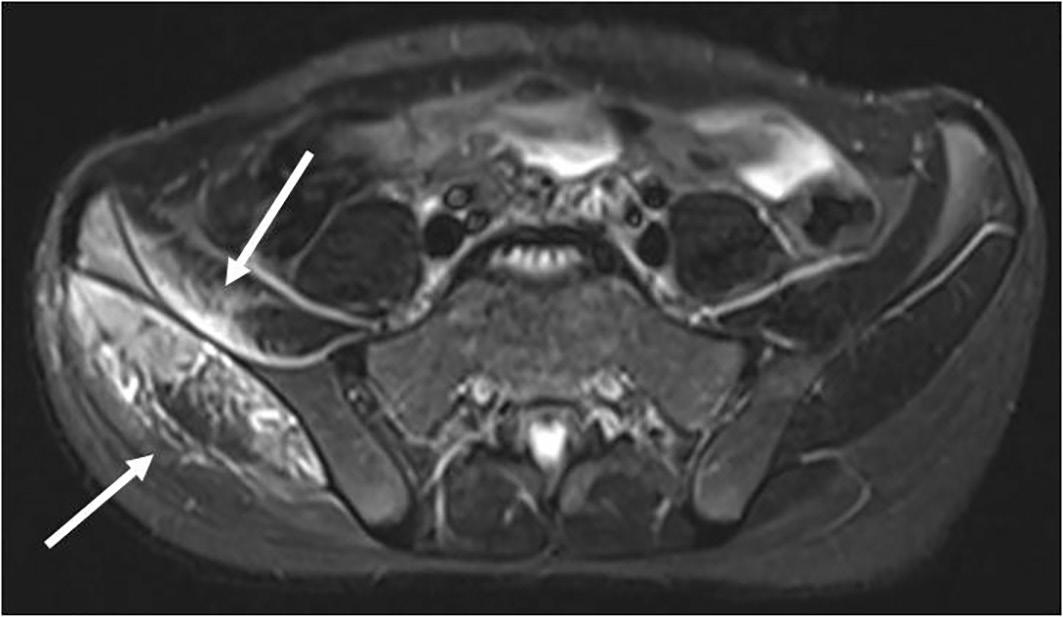

1 UO di Pediatria, Ospedale G.B. Morgagni – L. Pierantoni, AUSL della Romagna, Forlì; 2 Scuola di Specializzazione in Pediatria, Università degli Studi di Ferrara

La piomiosite – inizialmente conosciuta come patologia prevalentemente tropicale e oggi ben presente anche nelle zone temperate – è un’infezione suppurativa del muscolo scheletrico che può originare da un traumatismo o da un’intensa attività fisica che determina un danno della struttura muscolare. Spesso sostenuta da Staphylococcus aureus , entra in diagnosi differenziale con l’artrite settica, l’osteomielite e la cellulite. La descrizione di un caso osservato in un giovane atleta ci consente di ripercorrerne gli elementi diagnostici e terapeutici fondamentali.

Pyomyositis – initially known as a predominantly tropical disease and now well present also in temperate areas –is a suppurative infection of the skeletal muscle that can originate from trauma or intense physical activity that causes damage to the muscle structure. Often sustained by Staphylococcus aureus , it enters a differential diagnosis with septic arthritis, osteomyelitis and cellulitis. The description of a case observed in a young athlete allows us to retrace the fundamental diagnostic and therapeutic elements.

La storia di Sergio Sergio, ciclista dilettante di 11 anni, viene in pronto soccorso per la comparsa di dolore elettivo a livello della cresta iliaca di destra da circa quattro giorni, associato a zoppia e febbre (TC max 38,5 °C) da un giorno, scarsamente responsiva agli anti piretici. Riferisce inoltre alcuni episodi di vomito alimenta re. Non riporta di avere subito traumi significativi. Il ragazzo è, complessivamente, in buone condizioni generali e a carico dell’articolazione coxo-femorale di destra non ci sono segni di infiammazione locale né limitazione ai movimenti di intra- ed extrarotazione. Lamenta dolore solo alla digitopressione del la regione antero-superiore della cresta iliaca di destra. La re stante obiettività è nei limiti della norma. Tra gli esami, emo cromo, funzionalità epatica e renale sono nella norma con un incremento della PCR (58,1 mg/L) e negatività della sierolo gia per parvovirus B19, CMV, EBV, micoplasma, bartonella e Widal-Wright. Anche la radiografia del bacino non evidenzia lesioni ossee.

Nell’ipotesi di un’osteomielite acuta si avvia trattamento con oxacillina per via endovenosa. Dopo 72 ore di terapia antibio tica, persistendo la febbre e pervenuta la positività dell’emo coltura per Staphylococcus aureus multisensibile, si sostitui sce la terapia in atto con la clindamicina per via endovenosa. In quarta giornata di ricovero la RM del bacino mostra estesi fenomeni di infiltrazione edematoso-flogistica con alcuni fo colai ascessuali che interessano soprattutto il muscolo medio gluteo e in minor misura l’ala iliaca destra [Figura 1]. Il qua dro è complessivamente suggestivo di piomiosite con inizia le coinvolgimento del periostio e dell’osso. Durante la degen

Figura 1. RM all’esordio che mostra l’interessamento infiammatorio del muscolo medio gluteo e dell’ala iliaca destra.

za Sergio migliora progressivamente riuscendo a deambulare seppure con gli ausili e resta apiretico dalla sesta giornata di trattamento. Dopo 16 giorni complessivi di terapia antibiotica endovenosa, gli esami mostrano la completa negatività degli indici di flogosi, l’ecografia muscolare rileva un’apprezzabile riduzione dell’area di infarcimento edematoso-flogistico sen za più evidenza dei focolai ascessuali. Il ragazzo viene dimesso con indicazione a proseguire la terapia con clindamicina per via orale per un totale di 21 gg. La RM, eseguita a distanza di un mese dalla precedente, documenta un significativo miglio ramento del quadro flogistico-suppurativo a carico del mu scolo medio gluteo, rimanendo solo una circoscritta area di interessamento nelle porzioni più craniali in adiacenza dell’a la iliaca. La terapia antibiotica viene proseguita per altre tre settimane e l’ulteriore RM a due mesi dall’esordio conferma la pressoché totale risoluzione dell’interessamento muscolare e osseo [Figura 2].

Quello che c’è da sapere sulla piomiosite (PM) Inizialmente descritta, alla fine dell’Ottocento, come miosite tropicale perché particolarmente frequente (1-4% dei ricove ri ospedalieri) nelle regioni tropicali subsahariane e in Brasi le, Giappone e Uganda, la PM è una patologia che colpisce più frequentemente adolescenti e giovani adulti anche se può in sorgere in tutte le fasce di età, con una maggiore incidenza nel sesso maschile. La sua crescente diffusione, anche nelle regio